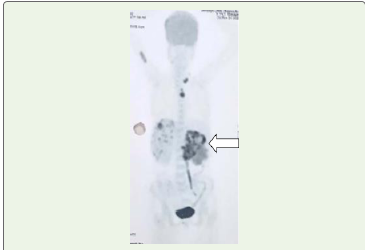

PET-CT demonstrated FDG-avid uptake within the left renal

mass, ureteric extension, renal vein involvement, and vesicoureteric

junction lesion [Figure 4], FDG uptake was also seen in few left

supraclavicular and mediastinal nodes. Intermediate uptake was seen

in the right proximal humerus, supporting a diagnosis of multicentric

urothelial malignancy with metastatic disease.

Figure 4:PET CT Image shows hypermetabolic mass lesion (white arrow)

in the left kidney extending into left renal pelvis and left ureter and infiltrating

into the left renal vein. FDG uptake is seen in few left supraclavicular

and mediastinal nodes. Intermediate uptake is seen in the right proximal

humerus.